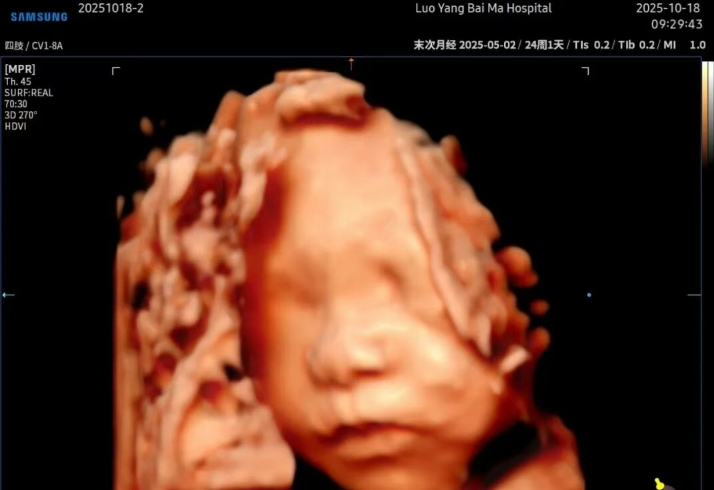

5D彩超+AI成像:揭开胎儿影像学的新篇章

洛阳白马医院5D智能彩超,是目前先进的超声诊断技术,

广泛运用于对胎儿进行超声检查,具有智能化大数据分析诊断和人性化智能交互应用功能,

相比四维彩超,在排畸功能上更完善、观察范围更广、画面更清晰,能够多方位、

多角度观察宫内胎儿生长发育情况。

能栩栩如生的显示您未出生的宝宝在妈妈肚子里的实时动态。

洛阳白马医院5D智能彩超+AI成像增值服务套餐,

通过四维彩超中宝宝的脸型,头型,五官位置等信息,利用人工智能算法,

大致测算并画出宝宝的样子,预测宝宝出生后的长相,并且将宝宝的图片处理得更清晰、

皮肤质感更逼真,满足父母对宝宝第一张“写真”的美好期待。